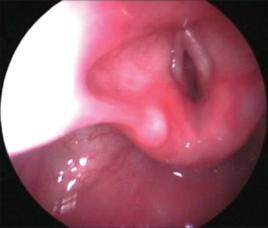

2、局部檢查急性炎症性喉水腫可見喉黏膜廣泛紅腫並附以分泌物。非感染性喉水腫黏膜呈蒼白水腫狀,杓會厭襞、聲帶尤為明顯。遺傳性血管神經性喉水腫有數小時發病,一般72h後逐漸消退的特點。

(1)感染性:可於數小時內發生喉痛、聲嘶、喉喘鳴和呼吸困難,並可伴發熱惡寒,咽喉疼痛,喉鏡下可見黏膜呈深紅色水腫、表面發亮。

(2)非感染性:可有誘因或有原發病,變應性和遺傳血管性尤其發病迅速,發展較快,患者常於數分鐘內發生喉喘鳴,聲嘶,呼吸困難,甚則窒息,喉鏡下可見喉黏膜瀰漫性水腫,蒼白。